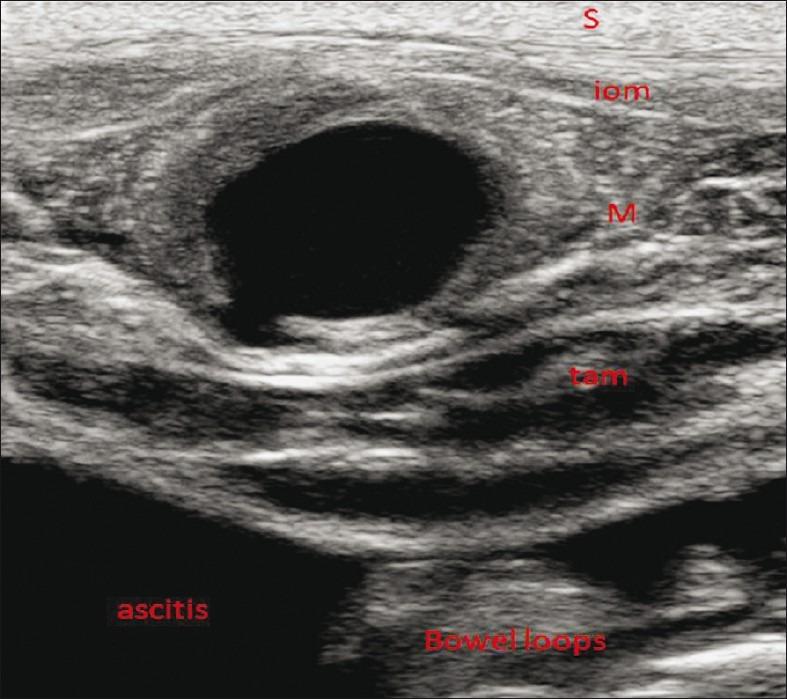

We report a case of a pseudoaneurysm arising from the deep circumflex iliac artery, in an end-stage renal disease patient with gross ascitis, presenting with an anterior abdominal wall hematoma following paracentesis. Duplex Doppler sonography confirmed the presence of the pseudoaneurysm and multidetector computed tomography angiography delineated the detailed arterial anatomy.

我们报告一例终末期肾病合并大量腹水患者,其髂外深动脉出现假性动脉瘤,在腹腔穿刺术后出现前腹壁血肿。双功多普勒超声检查证实了假性动脉瘤的存在,多排计算机断层扫描血管造影描绘了详细的动脉解剖结构。